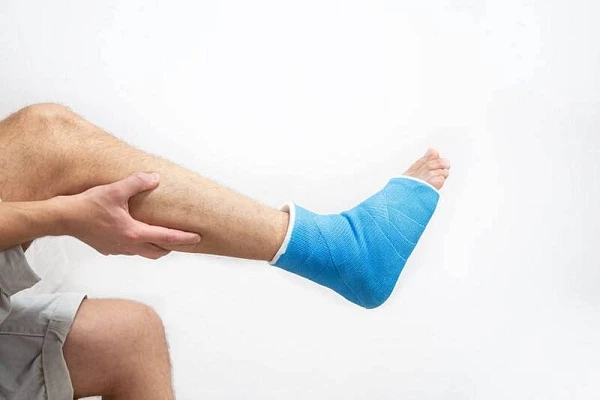

Консервативное проводится, если смещения нет или оно минимальное. Врач может провести репозицию под местной анестезией, а затем наложить гипсовую повязку или современную полимерную иммобилизацию (легкую, водонепроницаемую, гипоаллергенную). Это обеспечивает покой кости — главное условие для сращения.

Сращение кости — это только первый этап. Восстановление функции конечности требует системного подхода. В клинике «Центральная поликлиника на Ленинградке» разработана комплексная реабилитационная программа, включающая:

• лечебную физкультуру под руководством реабилитолога;

• физиотерапию (магнитотерапия, УВЧ, электрофорез) для ускорения регенерации;

• массаж для улучшения кровообращения и предотвращения атрофии мышц.

Реабилитация начинается уже на этапе иммобилизации с простых упражнений для незафиксированных суставов. Это помогает избежать осложнений и вернуться к привычной жизни быстрее.